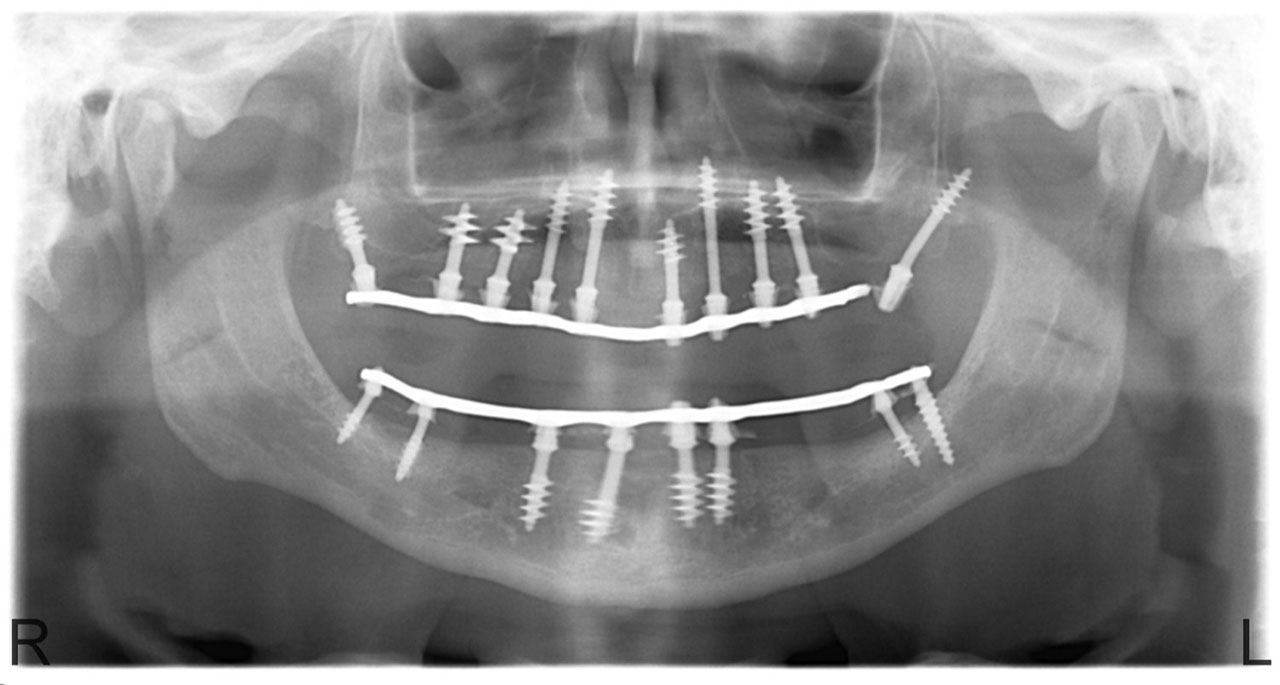

Teljes fogatlanság.

• esettanulmany-14

Alsó- felső fogatlan állcsont teljes implantációs helyreállítása.

Műtét másnapján, implantátumok a szájban.

• esettanulmany-09